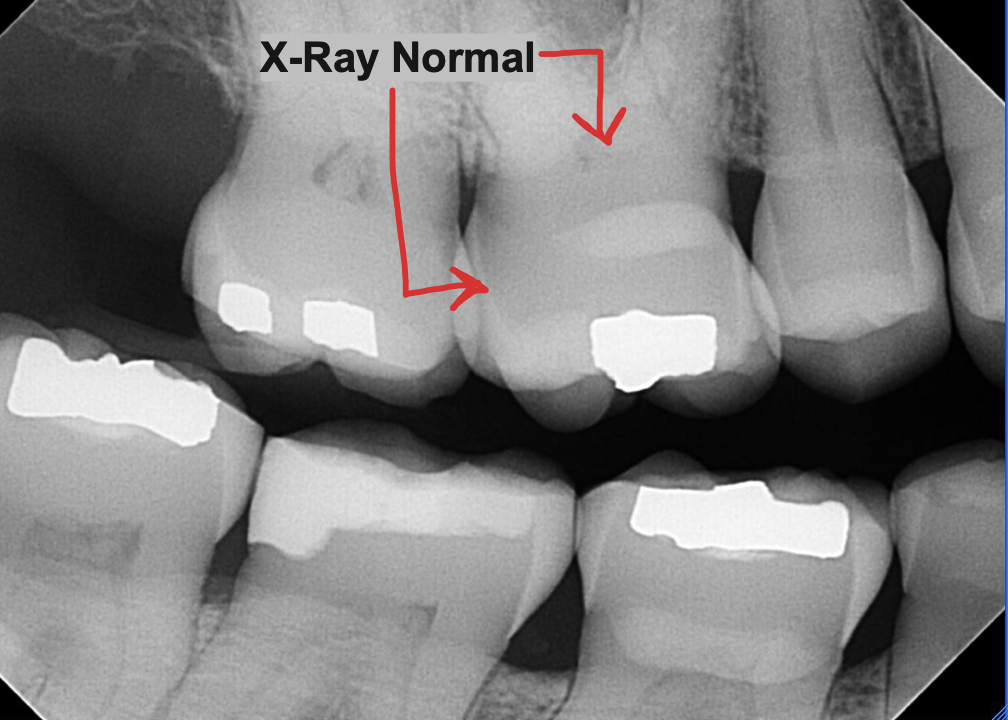

👀 Step 1: Pre-Op Evaluation

Before removing the tooth, we assessed bone health and root position with detailed imaging. In this case, the tooth had a prior root canal and a cavity on the back side, which caused the crown to loosen and eventually fall off. This tooth could not be saved by a new crown, so it needed to be extracted to prevent risk of infection and further damage of surrounding tissue. After reviewing alternative options, this patient is planning on a future dental implant to restore the site.

X Ray of tooth #18 Prior to Extraction

✅ Purpose: understand root formation, nerve anatomy, and ensure the socket walls are intact for grafting.

After the bone graft. Notice where the roots used to be, the socket appears filled with bone particulate.